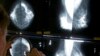

“Nxa umuntu engananzelela ukuthi uleqhubu ebeleni, uyahamba kudokotela okuthiwa ngu pathologist ozakhangela ukuthi imvukuzane le isifike kusigaba siphi. Imvukuzane ilezigaba ezisuka kustage zero kusiya kustage 4 ..."

Ulwazi ngemvukuzane yebele luqakathekile kakhulu ngoba lulakho ukuphathisa ekuphephiseni uzulu ekulahlekelweni ngumphefumulo.

“Imvukuzane eyebele ijayeleke kakhulu ukutholakala ebantwini abaleminyaka engu40 kusiyaphezulu, kungatsho ukuthi abangaphansi abayitholi. Intwenye esithanda ukuthi abantu bayinanzelele yikuthi iyatholakala ebantwini ngosendo.”